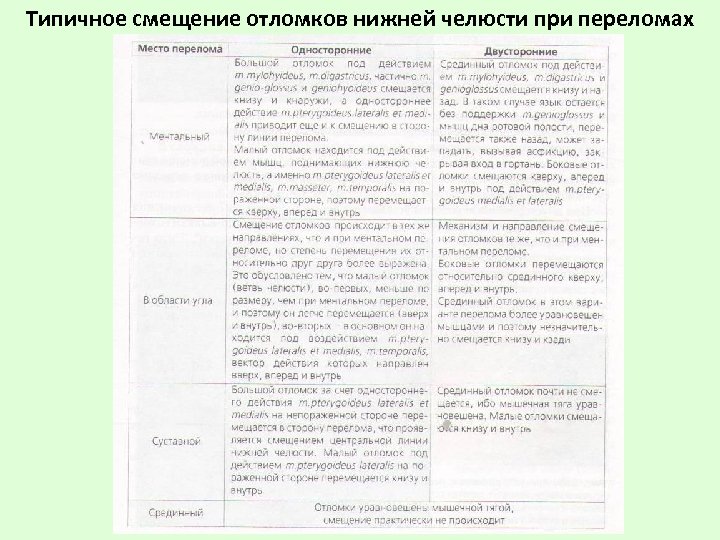

Типичное смещение отломков нижней челюсти при переломах